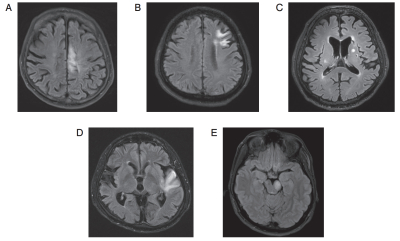

右利き患者の頭部単純 MRI の FLAIR 像を別に示す。

Wernicke 失語を認めるのはどれか。

a. A

b. B

c. C

d. D

e. E